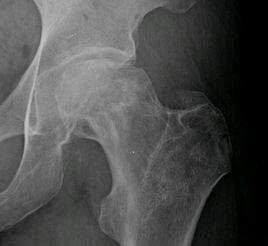

酒精性股骨頭壞死的X光片特點

酒精性股骨頭壞死多見於股骨頭頂部壞死病灶,呈全頭彌散慢性壞死。

酒精性股骨頭壞死的X線表現:

1.早期股骨頭外形完整,骨性關節面光滑,骨密度無明顯改變,僅見骨小梁梳松變粗,但臨床上無典型的臨床症狀及體症,並且在酒精性股骨頭壞死的早期X線光片並不能顯示股骨頭壞死,所以早期光靠X線光片診斷股骨頭壞死比較困難,則需要患者做ECT、MRI等檢查來輔助診斷。

2.中晚期在骨性關節面的下方出現了2-4mm寬的新月形透明帶,即"新月征"。股骨頭頂部或全股骨頭的密度增高,但有密度減低及囊狀透光區。死骨為楔形及半月形,其下有一密度較高的新生骨帶。股骨頭塌陷變形,呈蘑菇狀。骨形關節面破裂,凸凹不平,關節間隙變窄,患髖呈半脫位。常伴有骨性關節炎